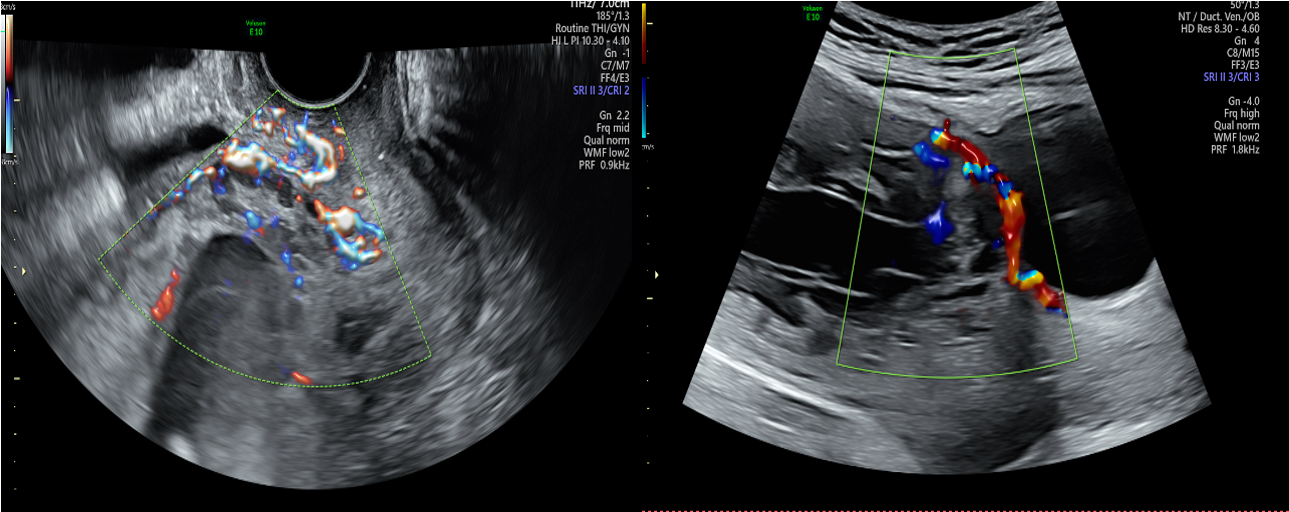

小彭在孕32+5周时,外院磁共振检查却提示未见胎盘植入,但B超始终提示胎盘内见数个液性回声,前壁峡部肌层内血流信号丰富,磁共振与超声的检查结果似乎不一致,患者及家属辗转苏州多家医院咨询相关风险,一路奔波,最后来到我院找到妇产科张跃明主任。张主任仔细阅读磁共振片子(图2),发现胎盘虽未完全覆盖宫颈内口,但整个胎盘位于子宫下段前壁及前次剖宫产疤痕处,子宫下段前壁肌层缺如,认为此例凶险性前置胎盘情况不可小觑。随后通过B超检查行胎盘植入评分为5分(≤5分为轻度),如果按胎盘植入分判断,可期待至37周终止妊娠即可,所需输血量较少,且无需其他学科参加。但张跃明主任凭借多年丰富的临床经验,结合磁共振图像及B超评价,认为情况远不如看上去一般轻松。目前产妇已孕36+4周,不能继续再期待,应立即收入院。

影像科及超声科医师先读片,张跃明主任分析该患者病情,提出手术过程中可能存在的风险及各科室需要做的工作。每个科室都提出自己独到见解及相关工作准备情况:输血科保证血源充足;介入科术前行髂内动脉预置管,必要时术中暂时栓塞阻断子宫血供;麻醉科术前留置动静脉导管以便监测生命体征及快速扩容输血抢救休克;泌尿外科随时待命台上会诊;ICU留床保障术后康复;儿科做好新生儿窒息复苏准备……

图2

图3